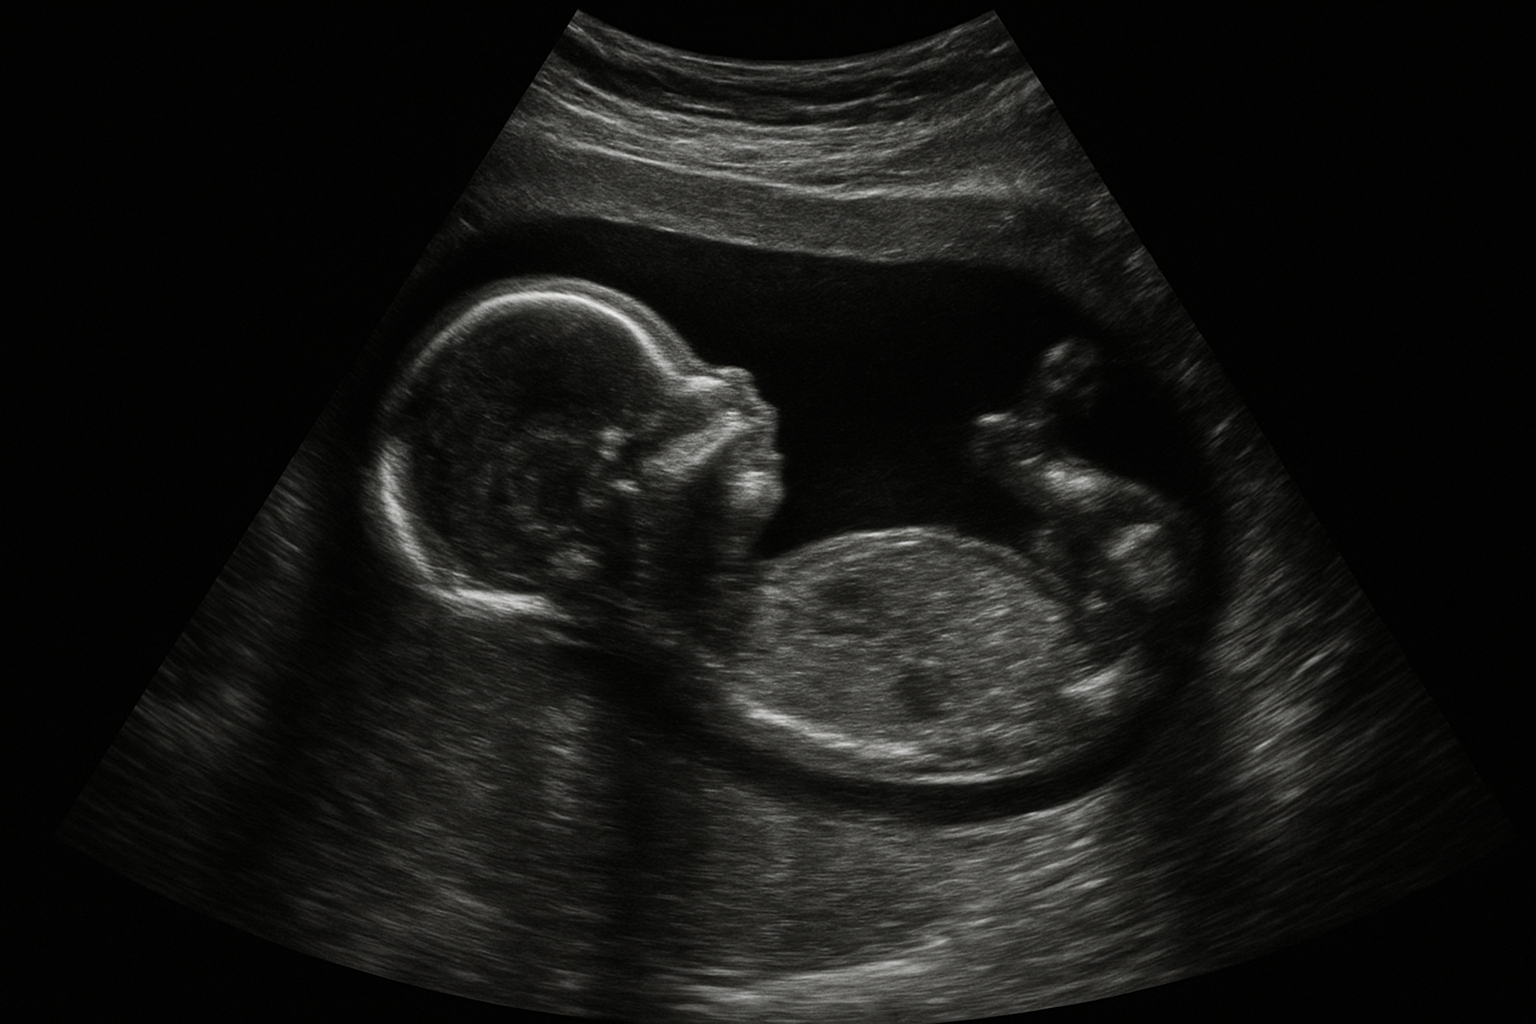

L’échographie 3d représente une avancée technologique importante par rapport à l’imagerie classique en 2d. Désormais, les parents découvrent leur bébé sous des angles inédits, profitant de clichés volumétriques où les traits du visage se dessinent nettement. La version 4d ajoute la notion de mouvement en temps réel, accentuant encore la dimension émotionnelle du moment et rendant la visualisation du bébé plus vivante.

Au fil de la période de grossesse, ce type d’examen s’inscrit souvent dans les habitudes pour mieux appréhender l’évolution du fœtus. Outre la visualisation du bébé, certaines familles apprécient l’aspect ludique qui entoure la première identification du sexe, même si cette information médicale n’est pas la finalité initiale de l’échographie.

Durant la deuxième échographie officielle – connue aussi sous le nom d’échographie morphologique – les professionnels de santé prennent le temps d’analyser minutieusement l’image pour garantir la fiabilité de l’échographie. Ce contrôle intervient couramment autour de la 20e semaine, car à ce stade, la différenciation sexuelle devient plus évidente.

Certains paramètres influencent la clarté de la visualisation du bébé et donc la possibilité de distinguer fille ou garçon. Le volume de liquide amniotique, la position du bébé et l’épaisseur abdominale de la future maman jouent tous un rôle clé dans la qualité des images obtenues. Les spécialistes recommandent parfois des scans supplémentaires si l’identification du sexe s’avère compliquée lors du premier essai.